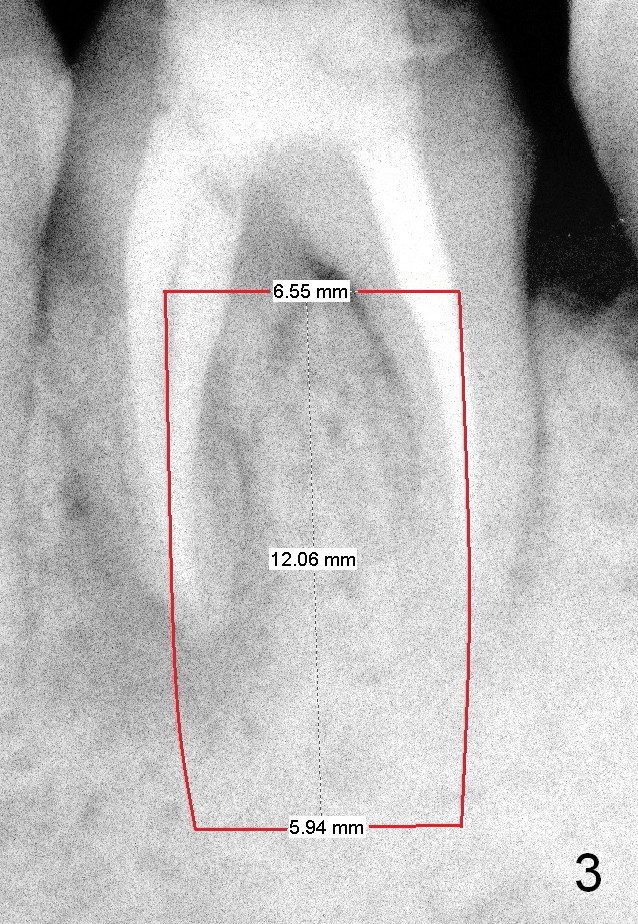

Where to place the immediate implant, septum (Fig.3), mesial or distal (Fig.4) socket? What is rationale?